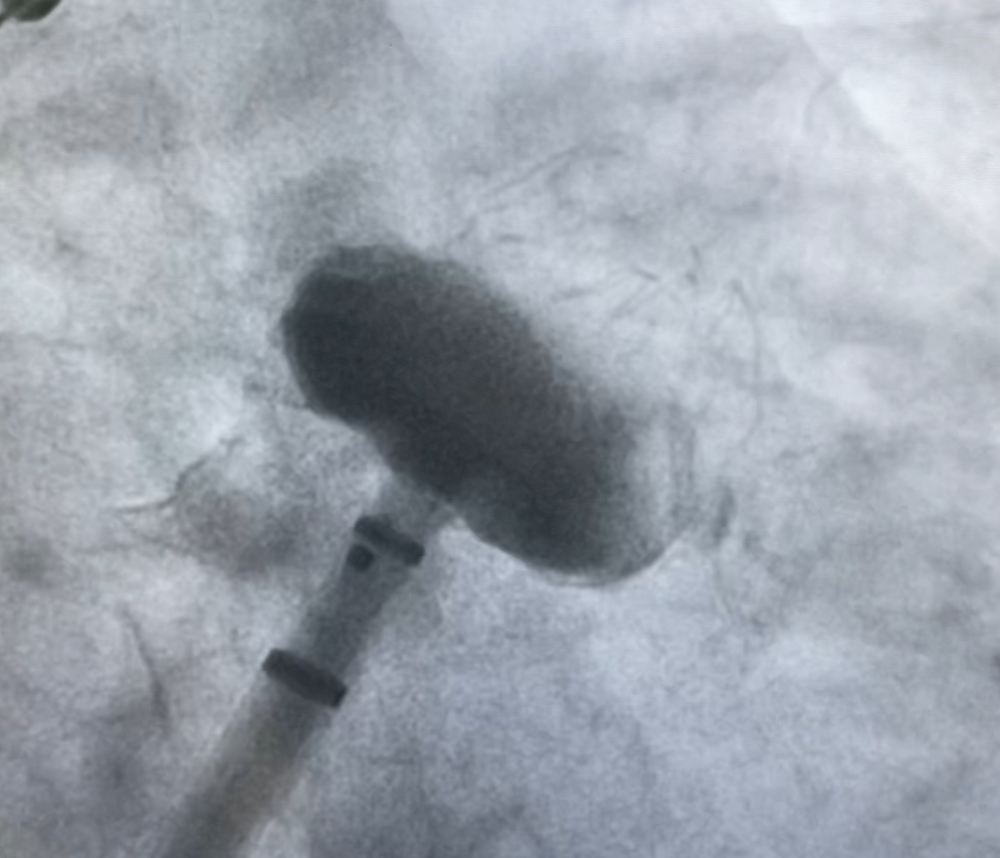

术中DSA造影测量图

术前王智勇教授带领综合内科张薇副主任团队,邀请麻醉手术中心王彩霞主任、ICU谢秀峰副主任等多名专家进行了深入、细致的病例讨论。医学影像中心王宗博医师,为患者完成了术前左心耳CT造影检查,测量了左心房尺寸、明确肺静脉解剖状况,为手术的顺利完成做了充分的术前评估。经团队综合评估,计划为该患者在行冷冻球囊房颤消融术后,行左心耳封堵术预防卒中。